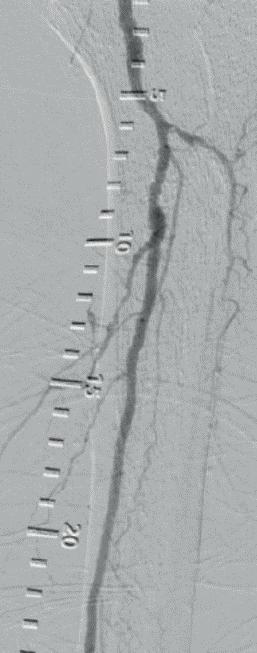

Figure 1: Diffuse calcified occlusive disease on pre-procedural arteriogram

a) Anterior tibial (AT) artery b) Dorsalis pedis (DP) artery

Figure 2: Shockwave Javelin in therapy a) In the AT b) In the DP

Figure

3: Definitive therapy, AT and DP treated with a 2.5x150mm angioplasty balloon a) Completion angiogram of AT b) Completion angiogram of DP